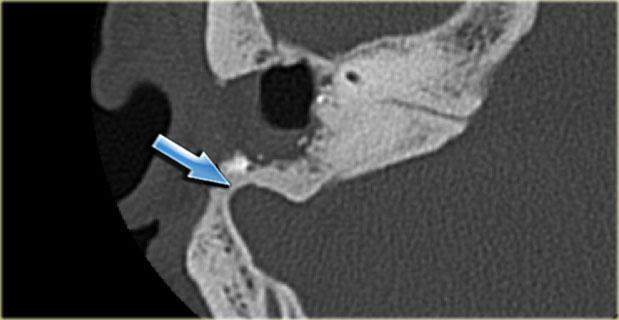

Bên trái là hình ảnh của một bệnh nhân nam 58 tuổi.

Mũi tên màu xanh chỉ cống ốc tai đi về phía ốc tai.

Hình ảnh này có thể bị nhầm lẫn với đường gãy xương (mũi tên).

Lưu ý có hình ảnh mờ đục của hòm nhĩ và các tế bào khí xương chũm.